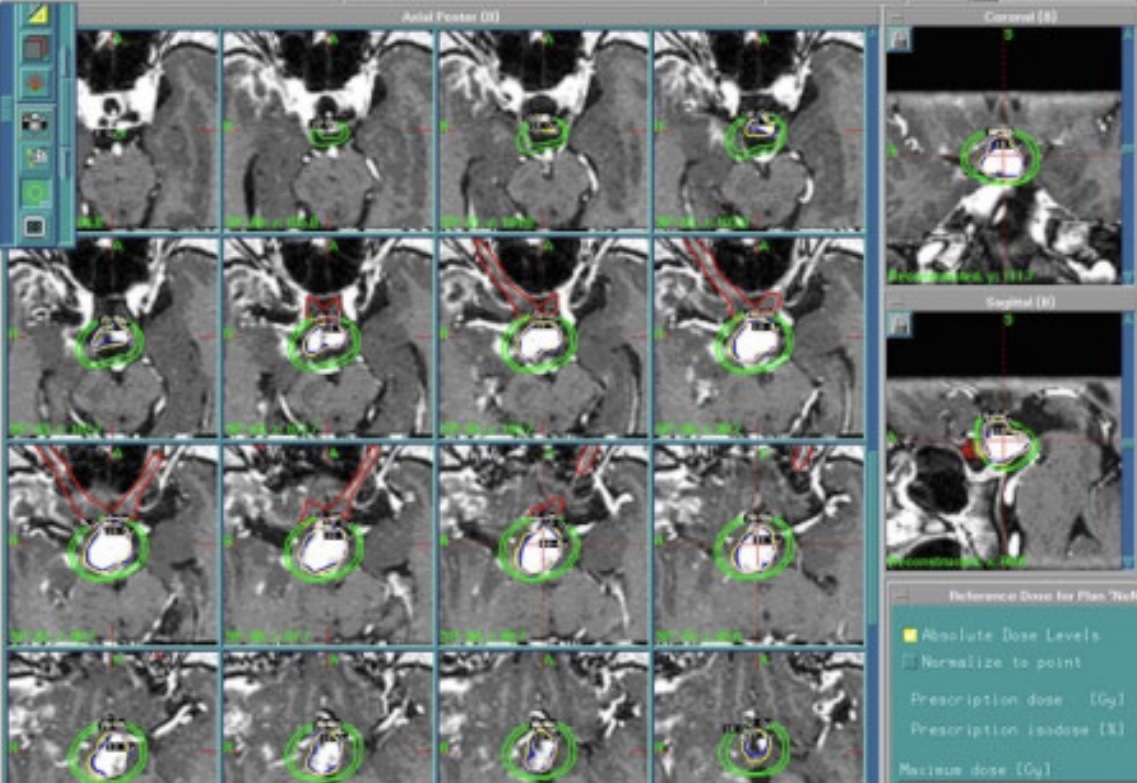

3.電腦療程規劃

加馬刀利用201根加馬射線,集中照射,患者不須打開顱骨,在單一的療程中,將幅射離子束,由四面八方集中照射顱內特定腦瘤,如同太陽光之聚光點,腦瘤接受極高的治療劑量,而周圍組織劑量減至最低,達到治療腦瘤不傷害腦組織的目的。